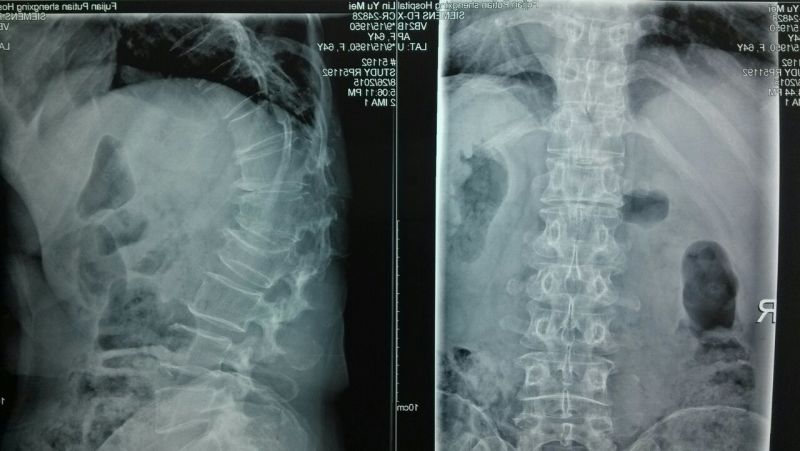

術(shù)前DR片

65歲的林阿婆是莆田市東埔鎮(zhèn)的一位地道農(nóng)民,因挑擔(dān)子后出現(xiàn)腰背部疼痛難忍,站立及行走時疼痛加劇,臥床時翻身困難,自行在家臥床休息10余天,疼痛仍不緩解。由家人攙扶求診我院。經(jīng)中醫(yī)科拍DR片、核磁共振檢查,診斷為:第二腰椎骨質(zhì)疏松性壓縮性骨折。